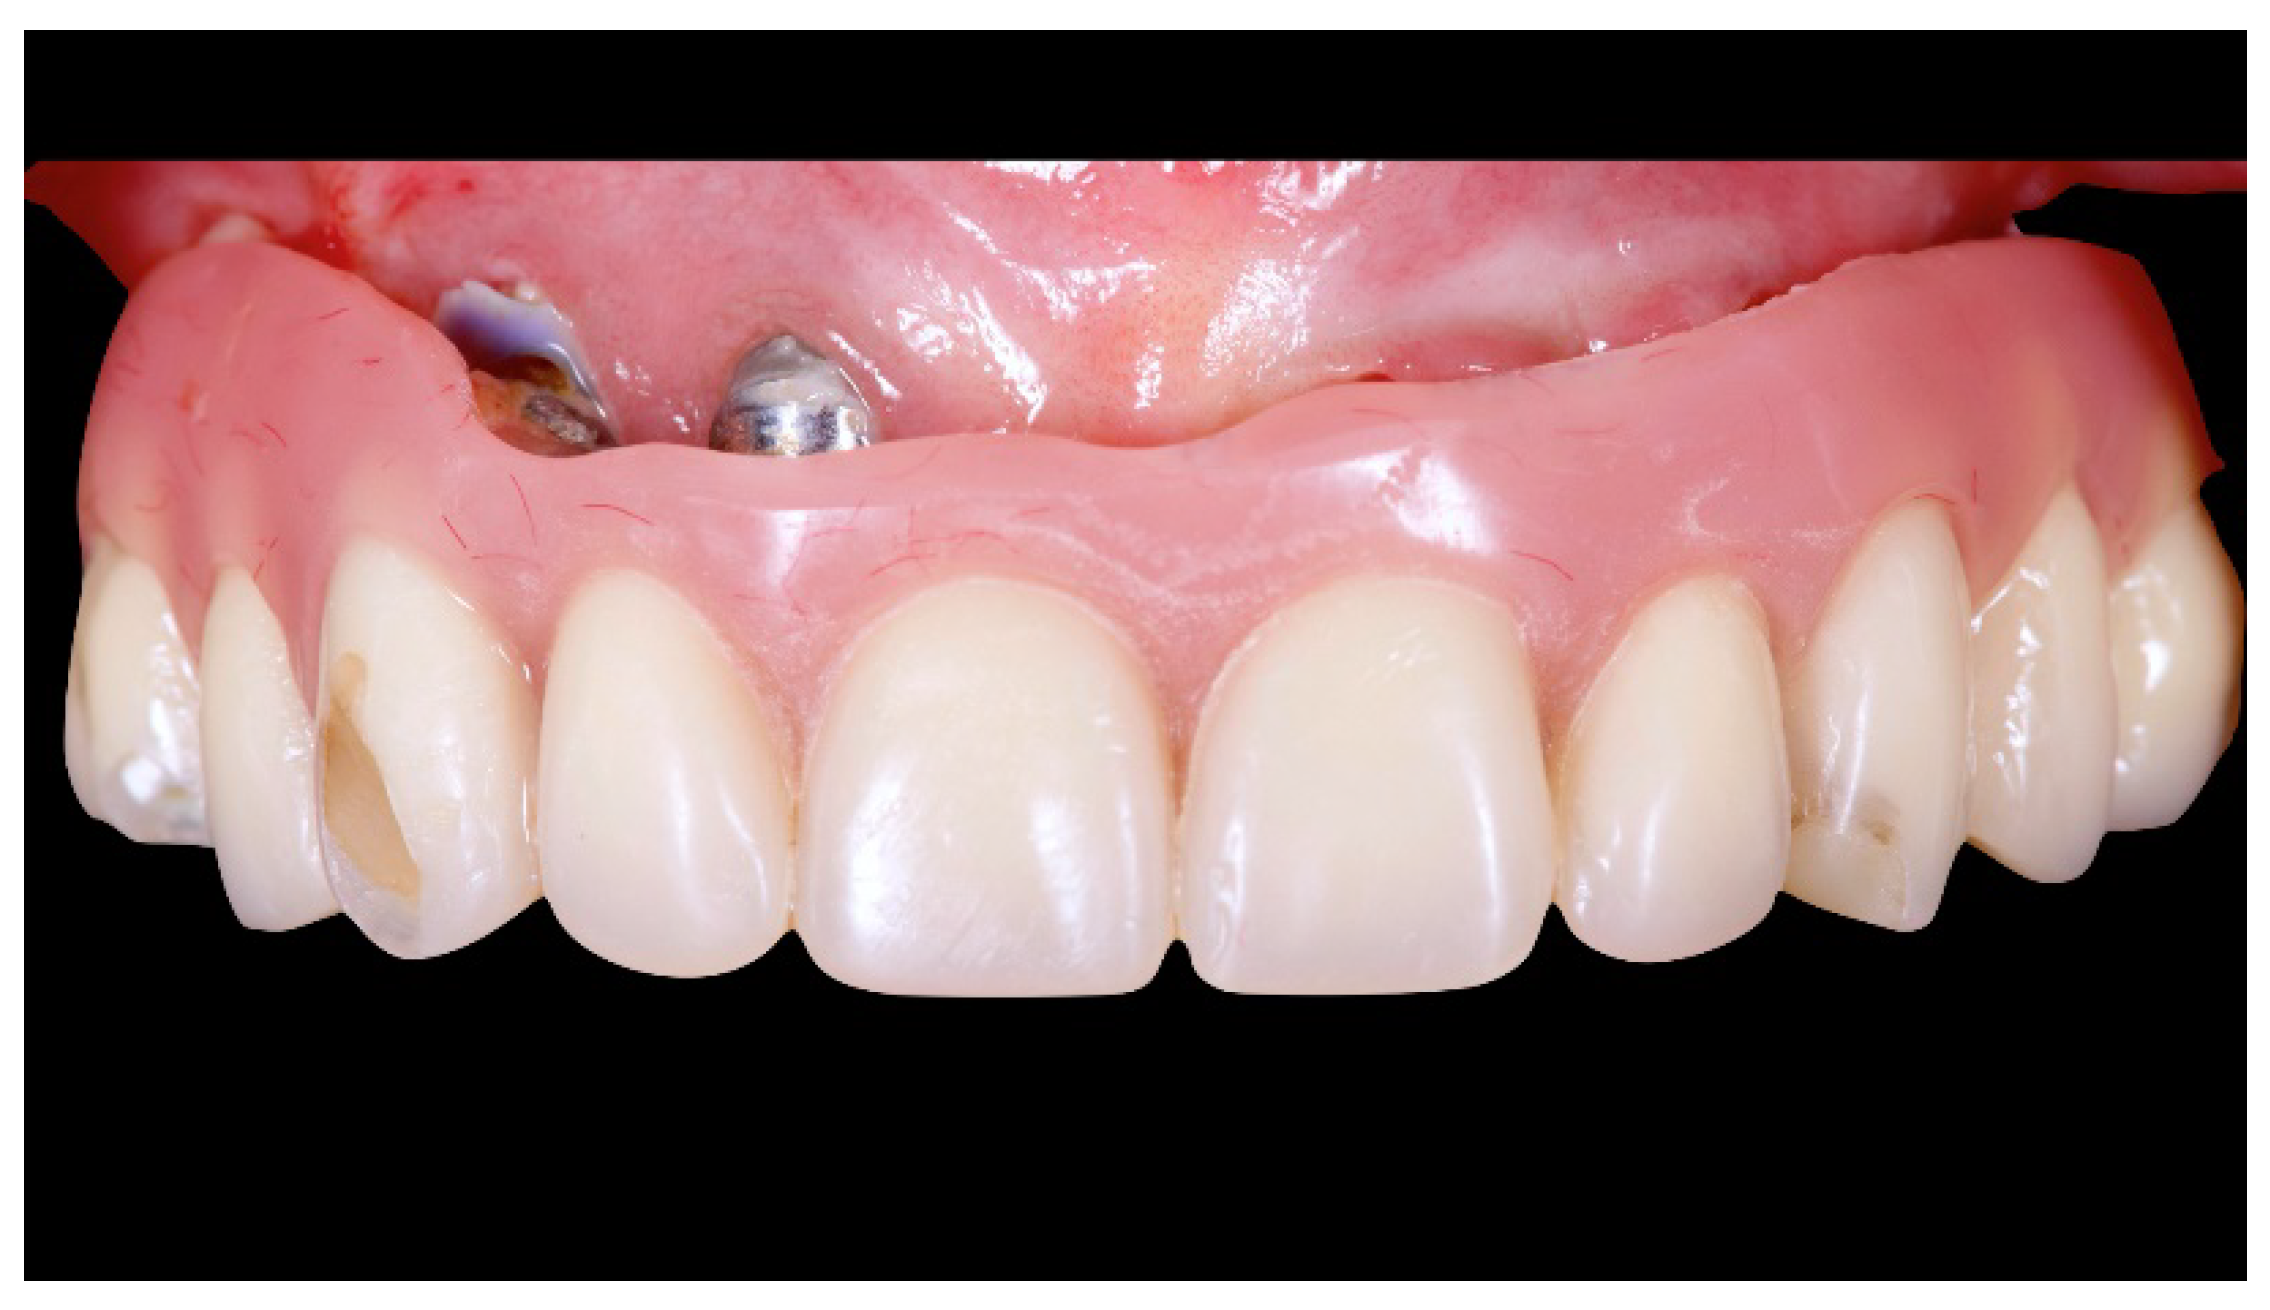

Figure 6.

OT Equator used as abutment for the fixed prosthesis according to the OT Bridge system.

Figure 7.

Scan bodies mounted on OT Equator. Note the strong disparallelism among the dental implants.